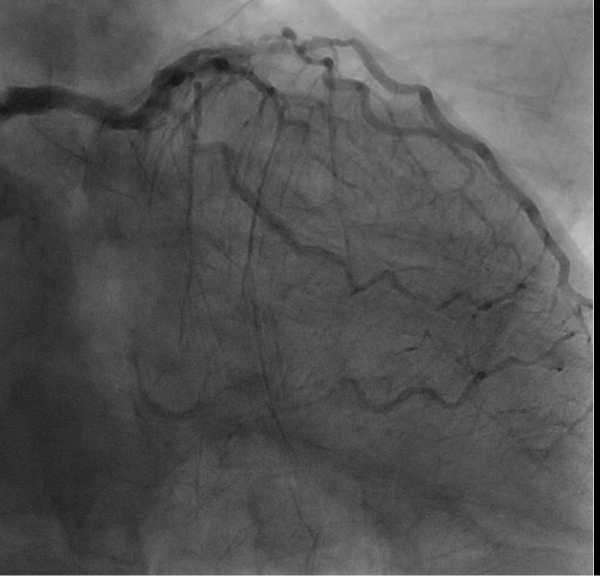

類天疱瘡でステロイド高容量内服中の3枝病変を有する患者。

胸骨正中切開では感染・前縦郭洞炎のリスクが高いと考え左側胸部小開胸でオフポンプ冠動脈バイパス術(MICS-CABG)を施行しました。

手術は左第5肋間・皮膚切開11センチで左内胸動脈-左前下行枝、コンポジットグラフトで左回旋枝‐右冠動脈をバイパスしました。

術後冠動脈CTでも良好なグラフトの開存を認めています。